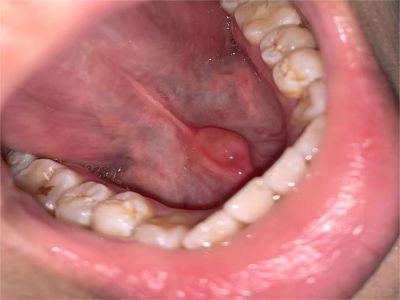

舌下腺囊肿舌底下长了个蚕豆大小的疙瘩图

舌下腺囊肿出现在舌系带一侧,表现为凸出于黏膜表面的疙瘩,如蚕豆大小,质地较软,有异物感,局部自发破溃,流蛋清样液体,常反复出现。